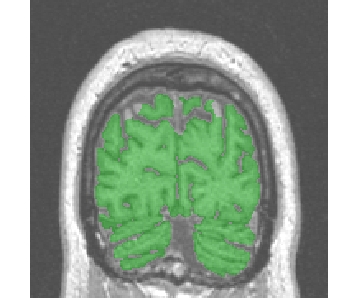

If the previous choices did not work, the problem may stem from some artifact hiding in some places the black areas corresponding to the skull:

In such cases, the initial binarization which is trying to fill small cavities resulting from noise has to be discarded, otherwise the skull is partly cancelled and the erosion has not a chance to do its job. Try the following variants:

"Standard/Robust... without regularisation"